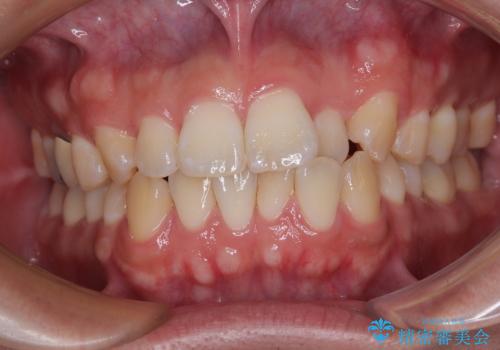

- 以前矯正治療をされていましたが、後戻りが起きたことを気にして来院された患者様です。

全体的に軽微な叢生が認められ、口元もやや前方に突出していたため、インビザラインでのIPR(歯と歯の間を削る)と歯列全体の後方移動によって歯並びを整えることとしました。

治療前には口元の突出感とでこぼこのみを気にされていましたが、治療を終えてみると咬み合わせが改善されて事を実感されていました。

歯並びが改善したことはもちろん、口元も十分に引っ込めることができ、患者様には大変満足していただけました。